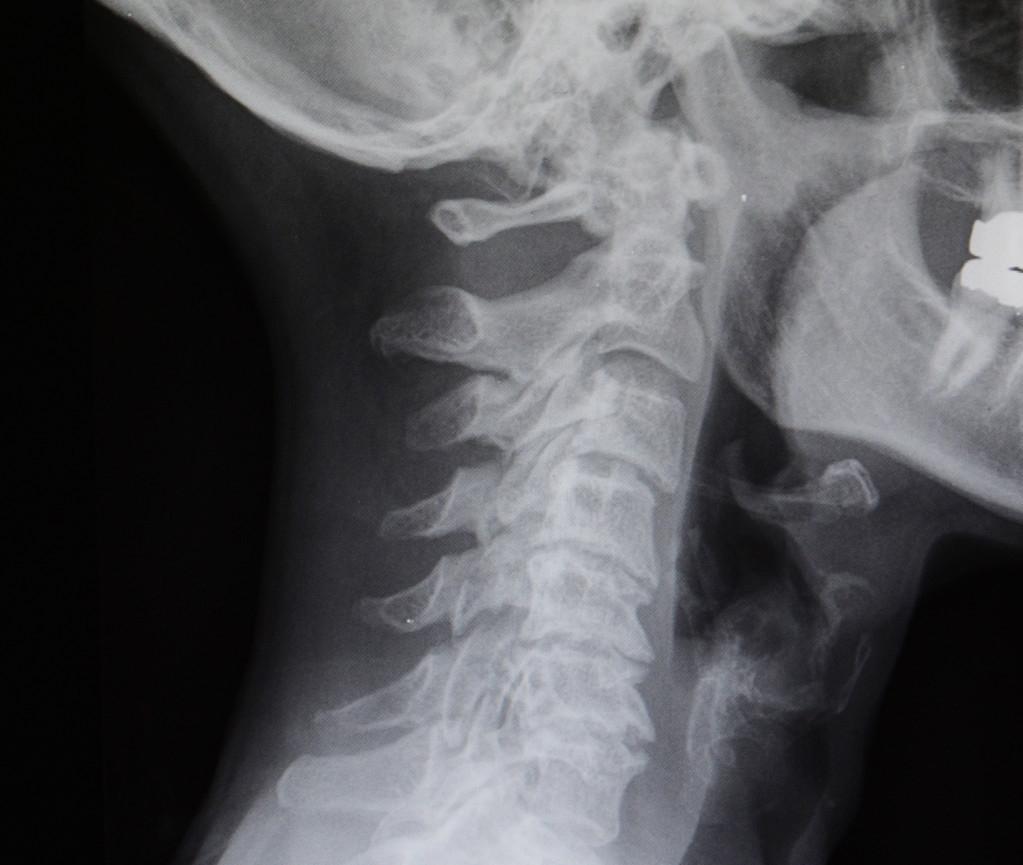

颈椎移位,这个可以理解,就是拍片的时候,发现颈椎有的椎体过度不自然,生理曲度也会有相应变化,例如,变直、反弓,还有的单节发生改变,这种人往往是最难受的,会头晕、恶心。

1.椎体的移位

颈椎椎体的移位,不同于颈椎小关节的紊乱,单纯的正骨是不行的,椎体发生改变先要看有没有经历过外伤,有的话处理起来也要慎重,椎体位置的改变,可以诱发很多不可预期症状,例如,走路和踩棉花一样,头晕、头昏昏沉沉。